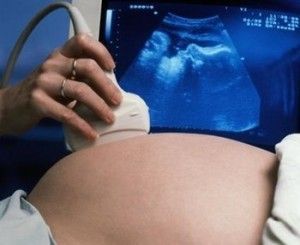

Durante la primera consulta hará una ecografía en la que la mamá tendrá la emoción de ver por primera vez a su pequeño. Se verificará que esté creciendo en el lugar correcto, sus medidas y se escucharán los latidos del corazón. Aparte de ello, el obstetra indicará la fecha probable de parto, recetará algún complejo vitamínico y ácido fólico, necesario para la sana constitución del bebé, y pedirá que se realice un análisis completo de sangre y de orina de la mamá.

En todos los controles el obstetra pesará a la mamá, le tomará la presión y le hará una ecografía para ver cómo evoluciona el bebé. Esto pasará una vez por mes hasta llegar a la semana 30 en que los controles serán cada 15 días. Luego de la semana 34 serán semanales. A partir de la semana 37 se realizarán monitoreos fetales. En el tercer trimestre es bueno que la mamá comience a acudir a un curso de pre parto, lo cual le ayudará a enfrentar exitosamente el momento de dar a luz.